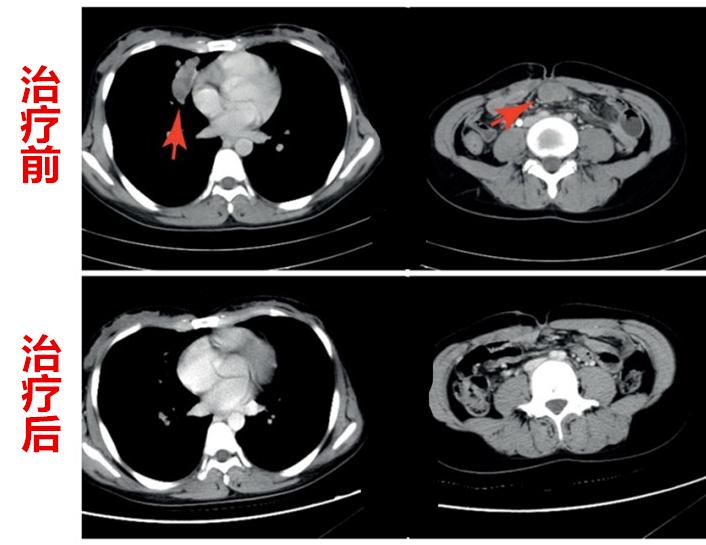

PD-1抗体和TIL联合治疗一月多后,王女士的肿瘤明显缩小,3个月后,肿瘤完全消失不见了(如上图所示)。

更加让人欣喜的是,应用3次PD-1抗体后,王女士停止了治疗,但肿瘤一直没有复发。

1个多月后,肿瘤明显缩小,3个月后,肿瘤完全消失(如上图所示)。

李女士的治疗至今已超过了2年,肿瘤处于完全缓解状态。